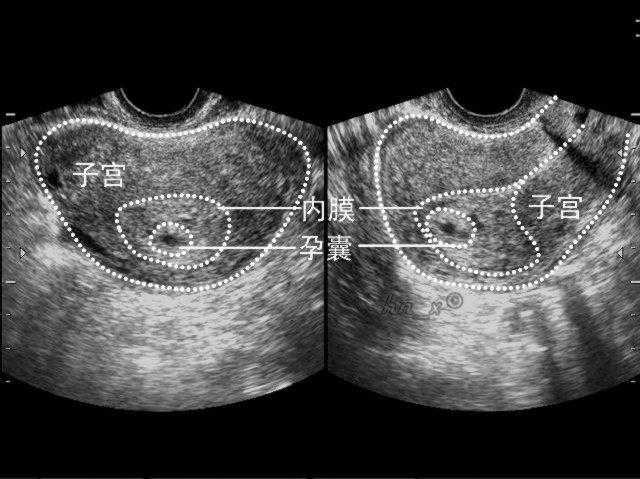

试管婴儿双胞胎和单胎的过程是一样的,只是在胚胎移植的时候可能会多移植1~2个胚胎。但是必须要知道的是,试管婴儿并不是你想要几胎都可以实现的,医生会按照您的身体情况来做评估,如果您是子宫环境放两个是最好的,那医生绝对不会帮您放三个,如果不根据身体情况来放置胚胎的个数,那就很容易弄巧成拙。

因为并不是每个人都是适合怀双胞胎的,是否能怀双胞胎是需要根据子宫大小、子宫内膜各方面情况才能决定的。因为有些子宫小、身体差的人怀即使怀上双胎,医生也有可能会建议减胎,因为怀双胞胎可能会威胁到母体的健康。